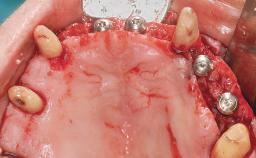

Conventional Loading of Eight Implants in the Maxilla and Final Restoration with a Full-Arch Gold-Ceramic FDP

A 35-year-old Caucasian female presenting with advanced periodontal disease involving both the maxillary and the mandibular dentition was referred for evaluation. The patient, a non-smoker in good general health, requested treatment for recurrent periodontal abscesses, tooth mobility, and discomfort during chewing, as well as restoration of her missing teeth with a fixed prosthesis to improve mastication and esthetics. All residual maxillary teeth exhibited plaque deposits, deep pockets, bleeding on probing, and class III mobility and were evaluated as hopeless. All residual mandibular teeth except tooth 37 could be maintained after periodontal therapy.